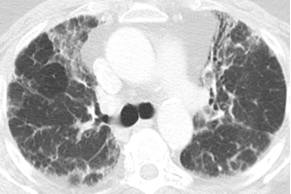

三种密度征(Three density pattern)里的三个区域分别是:高密度区提示磨玻璃影子,低密度区提示小气道疾病所累及的肺脏出现了气体陷闭的表现,还有一些正常的肺脏。

当出现三种密度征的时候,结合临床,能够高度提示这个患者是 HP。

这位慢性纤维化型过敏性肺炎患者就可以看到三种密度征、磨玻璃影、网格影、牵拉性支气管扩张,没有蜂窝。